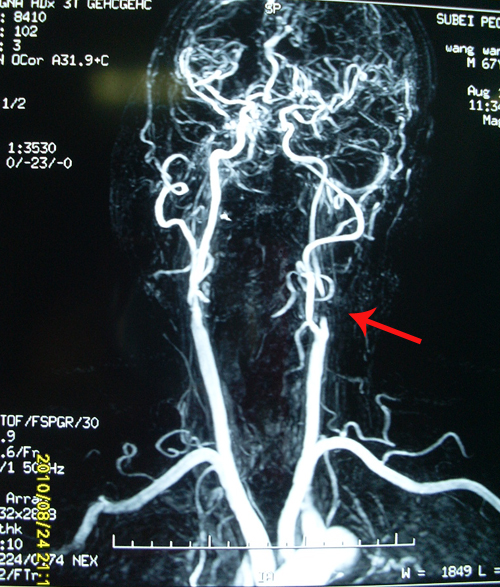

颈动脉超声:双侧颈动脉内膜增厚;左侧颈内动脉球部斑块形成延伸至颈内动脉近段局部狭窄(约90-99%),左侧颈总动脉阻力增高;右侧颈内动脉球部斑块形成延伸至颈内动脉近段局部管腔(约50-69%);右侧椎动脉颅外段血流阻力增高。